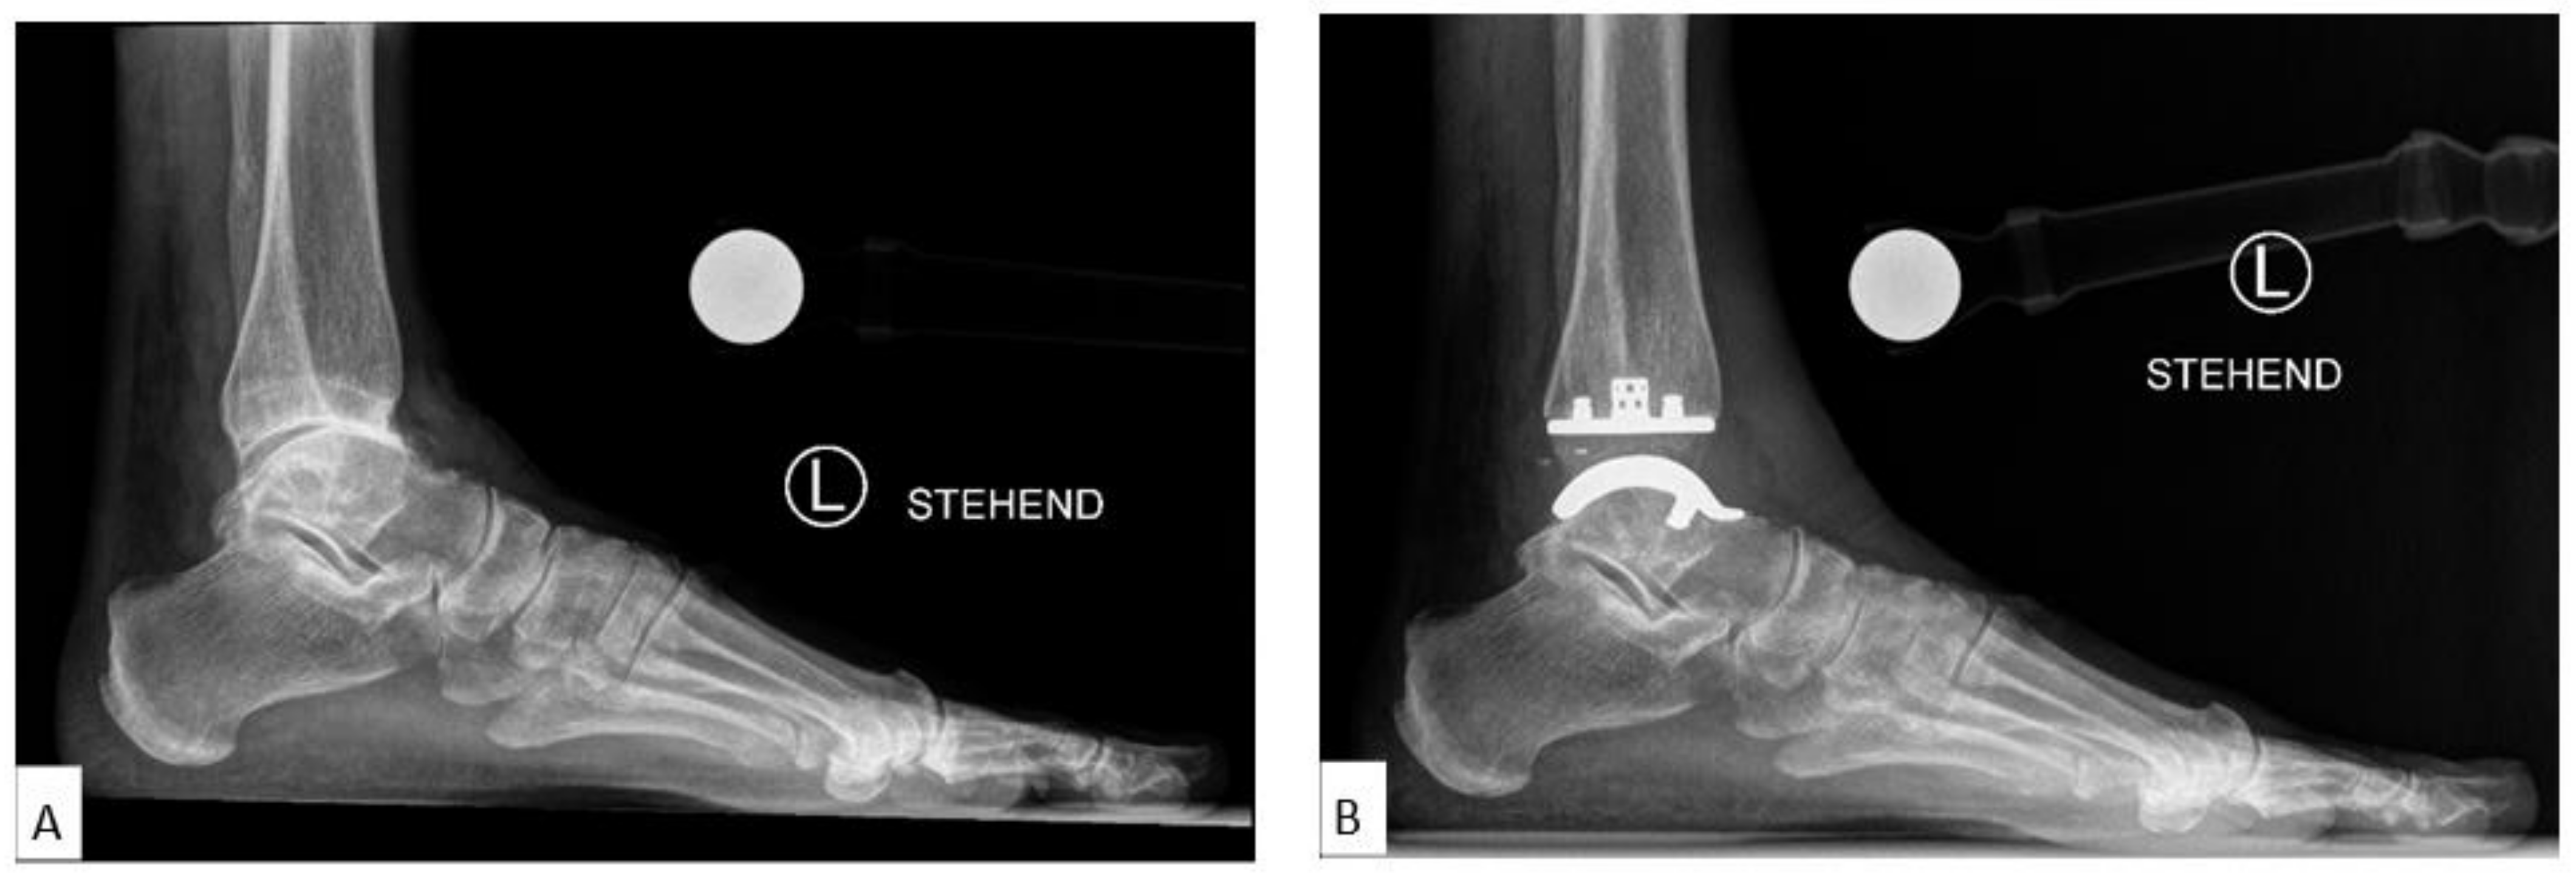

The medial distal tibial articular angle (mDTAA, degrees) [18] on the ankle OA as well as on the TAA as medial tibial component coronal angle were used to identify coronal alignment, measured on the anteroposterior radiograph as the medial angle subtended by the anatomic axis of the tibia and the tibial plafond line or inferior border of the tibial component, with positive values equal to valgus result and negative values equal to varus result (Figure 2A,B). The sagittal alignment assessed was by the anterior distal tibial articular angle (aDTAA, degrees) [19] on the ankle OA and on the TAA as anterior tibial baseplate angle [14,20] on the lateral radiograph, measured as the anterior angle formed from the anatomic axis of the tibia and the line connecting the distal points on the anterior and posterior tibial articular surface or inferior border of the tibial component (Figure 2C,D).

Figure 2.

Preoperative and Postoperative Radiological Measurements. (A): Medial distal tibial articular angle (mDTAA) on the ankle osteoarthritis (OA), (B): Medial distal tibial articular angle (mDTAA) on the total ankle arthroplasty (TAA) as medial tibial component coronal angle, (C): Anterior distal tibial articular angle (aDTAA) on the ankle OA, (D): Anterior distal tibial articular angle (aDTAA) on the TAA as anterior tibial baseplate angle. Lateral talar station (LTS). (E): Preoperative on the ankle OA, (F): Postoperative on the TAA.